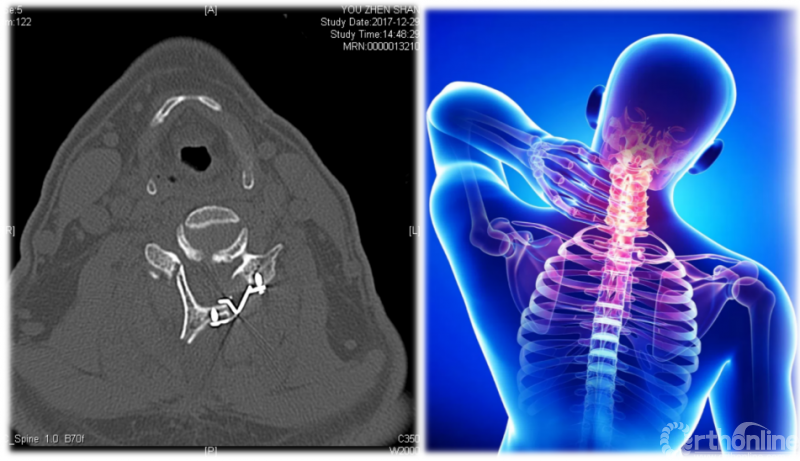

首先,我们要提到治疗颈椎管狭窄、颈椎后纵韧带骨化的经典术式——颈椎后路单开门椎管扩大成形术(ELAP)。因其脊髓功能改善明显、疗效持久等优点,已被骨科医师广泛应用于临床,然而有些患者在手术后出现了长期的颈项部及肩背部疼痛、僵硬,并伴酸胀、沉重感和肌肉痉挛,严重时甚至影响患工作与生活。1999年Kawaguchi首次将这种病态定义为轴性症状(AS)。

颈椎后路单开门椎管扩大成形术术后CT

轴性症状(axial symptoms)就是以颈背部疼痛为主要表现,伴有僵硬、酸胀、沉重感和肌肉痉挛的综合征。